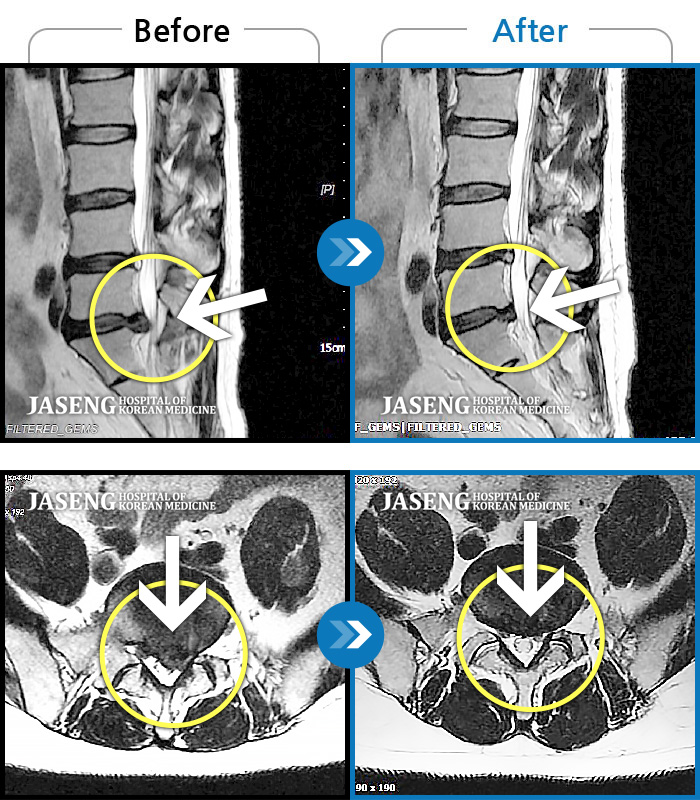

허리디스크

도움받은 사례

목동 · 고웅 원장

심한 허리 통증

촬영시기

2022.12.23 ~ 2024.12.04